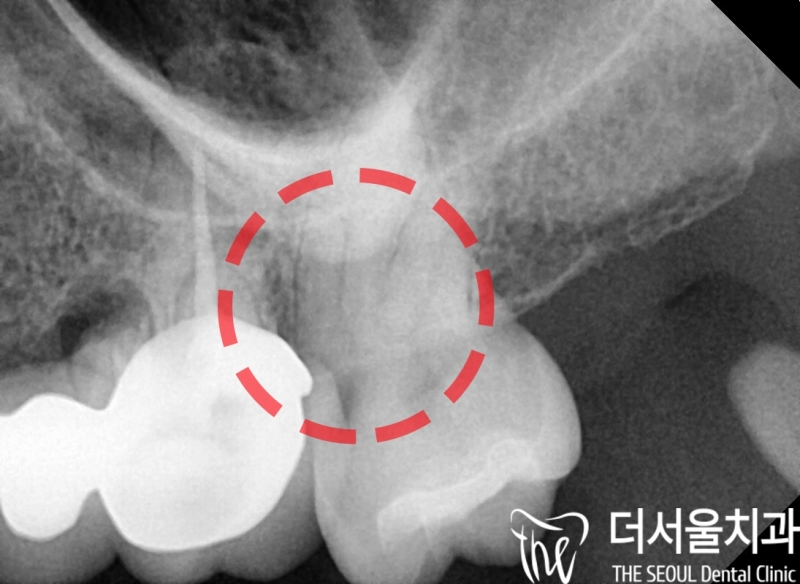

안녕하세요, 박현준 원장입니다. 오늘 보여드리는 임상 증례는, 크라운 수복으로 앞니 라미네이트 치료 처럼 한 임상 케이스입니다. 아래 사진으로